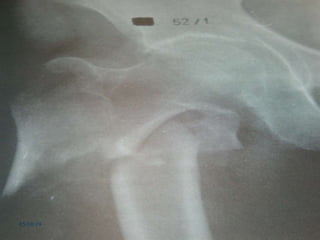

Imagenologia

 Exame radiográfico padrão

 Radiografia AP da pelve

 Radiografia AP do quadril

 Radiografia Lateral através da mesa de

exame, do fêmur afetado.

 *AP verdadeiro do Fêmur proximal

Imagenologia  Exame radiográficopadrão  Radiografia AP da pelve  Radiografia AP do quadril  Radiografia Lateral através da mesa de exame, do fêmur afetado.  *AP verdadeiro do Fêmur proximal 05/10/19 www.traumatologiaeortopedia.com.br